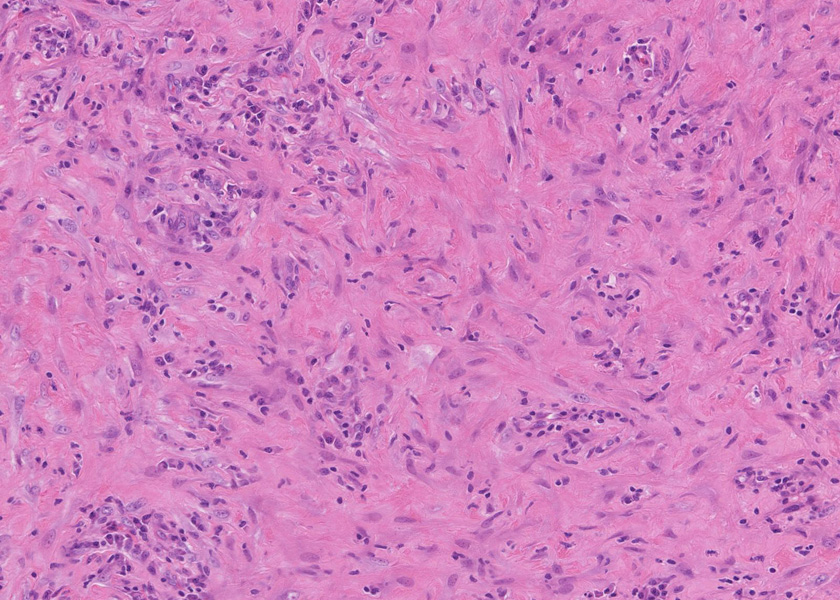

pancC.jpg

線維化組織に類円, 葉巻型淡明な核の紡錘型細胞が増生している。免染SMA陽性。血管周囲に慢性炎症あり。